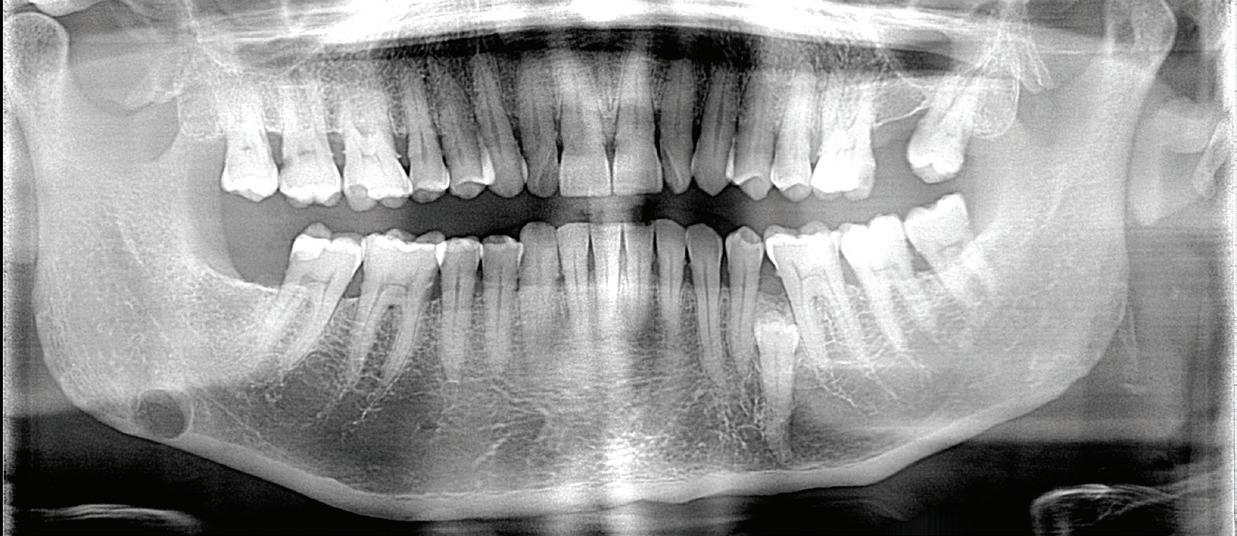

Clear aligner therapy and symptoms of temporomandibular disorders: a case report

Lina Sharab

Bushra Butul

Aqib Shafi

Jeffrey P. Okeson

SELF-INSTRUCTION EXERCISE GD538, 2 CE CREDITS, P. 53